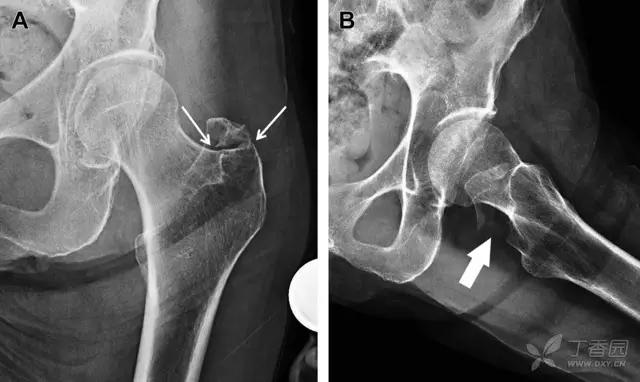

髋臼骨折最常见的类型是髋臼后壁骨折,几乎占髋关节骨折的 1/4,且常常合并髋关节后脱位。由于骨性结构重叠,可能肉眼看上去觉得非常轻微的骨折,事实却并非如此。髋臼后缘中断常常是髋臼后壁骨折的一个特征(图 2)。

图 2 为髋臼后壁骨折伴髋关节脱位患者。A 右侧髋关节 X 线片示股骨头后方可见一骨折线(箭头),髋臼后缘中断。B 左侧髋关节 X 片对照可见髋臼后缘连续(箭头)。C CT 三维重建图像示髋臼后壁缺损,可见旋转、移位的骨折块(箭头)